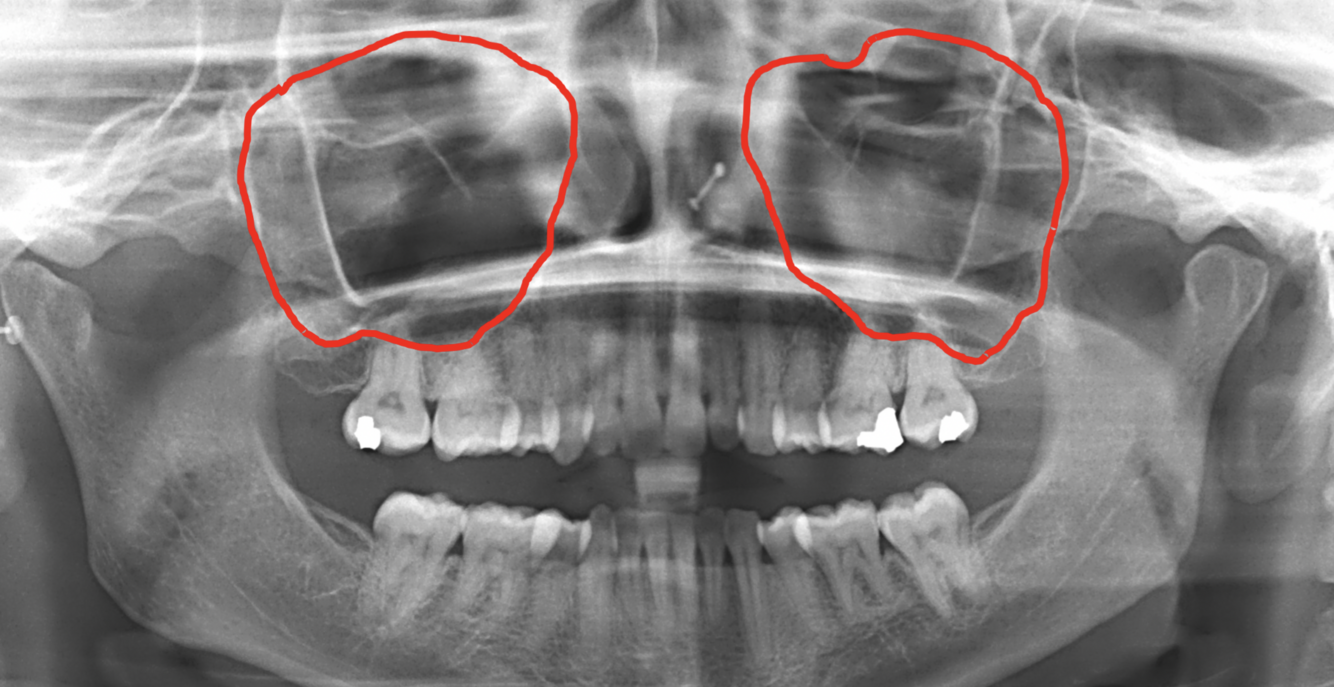

What is indicated by the red circles in the following image?

External auditory meatus